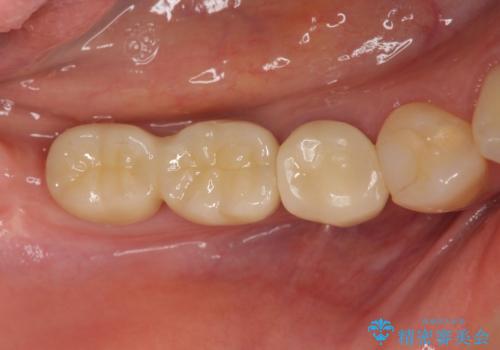

インプラント治療による咬合機能回復

- 失ってしまった奥歯の咬合機能の回復を求めて来院されました。

インプラントは高い確率で骨に結合し、しっかりとした咬合力を回復することができます。

長年安心してしっかりと噛んでいただけるよう今回は骨を増成する治療計画としました。